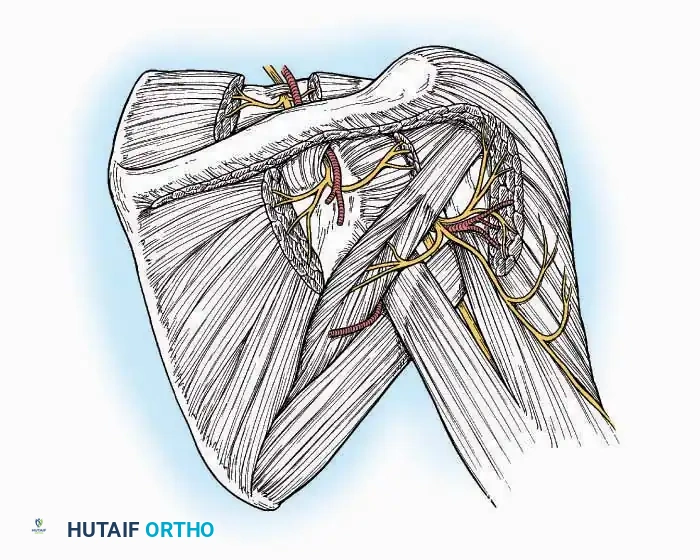

SURGICAL APPROACHES TO THE TARSUS AND ANKLE

Anterolateral Approach

The anterolateral approach is widely considered the "universal incision" for the foot and ankle. It provides unparalleled access to the ankle joint, the talus, and the majority of the tarsal articulations, while safely avoiding the major anterior neurovascular bundle. The only tarsal joints inaccessible via this route are the naviculocuneiform joints (specifically the medial and intermediate).

Indications: Total talectomy, triple arthrodesis, ankle arthrodesis, and open reduction of complex talar neck fractures.

Surgical Technique:

* Incision: Begin over the anterolateral aspect of the leg, medial to the fibula and 5 cm proximal to the ankle joint line. Carry it distally over the joint, crossing the anterolateral aspect of the talar body and the calcaneocuboid joint, terminating at the base of the fourth metatarsal.

* Superficial Dissection: Incise the superficial fascia and the superior and inferior extensor retinacula down to the periosteum of the tibia and the ankle joint capsule.

* Vascular Ligation: This trajectory usually requires the identification and ligation of the anterolateral malleolar and lateral tarsal arteries.

* Nerve Protection: Retract the skin edges carefully. Identify and protect the intermediate dorsal cutaneous branches of the superficial peroneal nerve (SPN), which frequently cross the distal aspect of this incision.

* Muscle Management: Identify the origin of the extensor digitorum brevis (EDB) muscle on the lateral calcaneus. Divide it in the direction of its fibers, or detach its origin entirely and reflect it distally to expose the subtalar and calcaneocuboid joints.

* Deep Exposure: Retract the extensor digitorum longus (EDL) tendons, the dorsalis pedis artery, and the deep peroneal nerve (DPN) medially. Incise the anterior ankle capsule to expose the tibiotalar joint.

* Tarsal Exposure: Expose the talonavicular joint by dissecting deep to the extensor tendons and incising its capsule transversely. Continue laterally through the capsule of the calcaneocuboid joint. By excising the fat pad within the sinus tarsi (lateral and inferior to the talar neck), the posterior facet of the subtalar joint is brought into direct view.